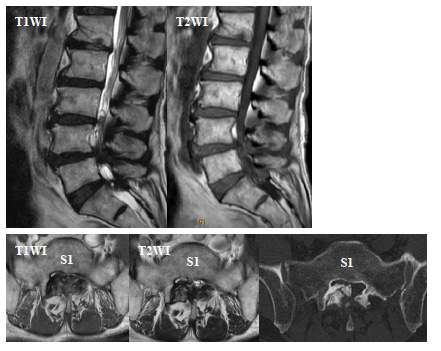

Magnetic resonance imaging (MRI) revealed spinal stenosis at C3/4, L4/5, and L5/S1 (Figs. 1 and 2). The right lesion at the level of L5/S1 appeared as a hyperintense area on both T1- and T2-weighted imaging in the thickened ligament flava. Computed tomography (CT) showed a high-density solitary lesion at this site, and we suspected an osseous tumorous lesion (Fig. 2).

Fig. (2). Magnetic resonance imaging (sagittal and axial views) and computed tomography (axial view) of the lumbar spine. T2WI and T1WI show L4/5 and L5/S1 stenosis and a solitary lesion that is hyperintense on both T1WI and T2WI in the thickened ligament flava. Computed tomography reveals an osseous solitary lesion in the canal. T2WI, T2-weighted imaging; T1WI, T1-weighted imaging.